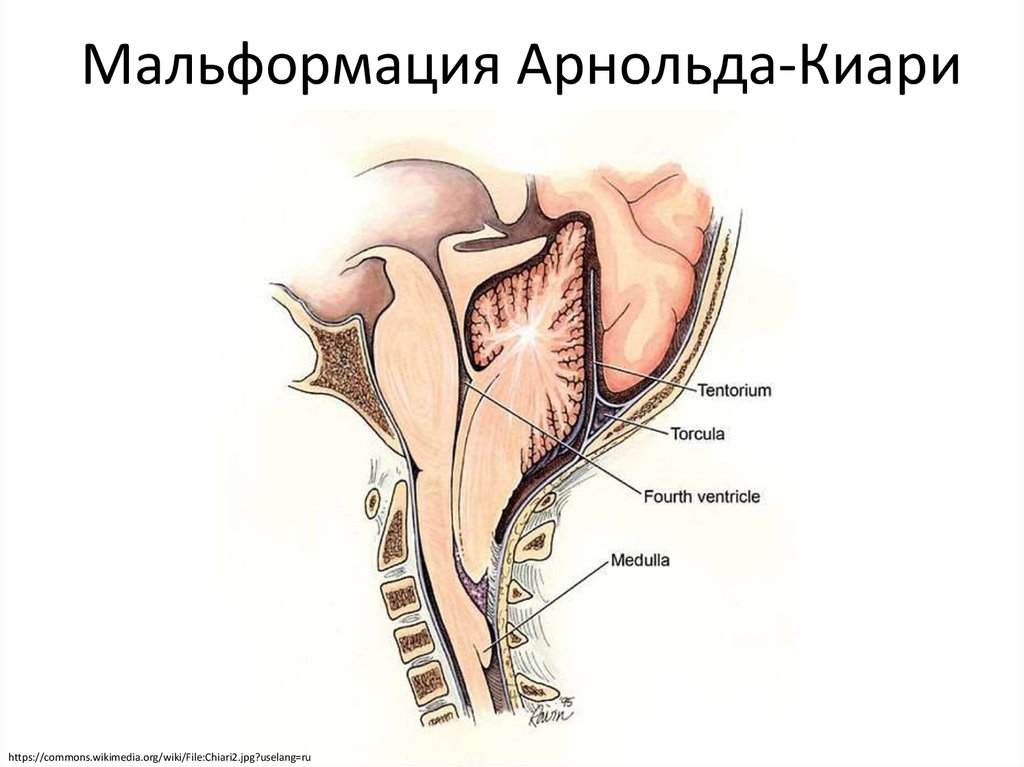

Аномалия Арнольда-Киари: MRI снимки